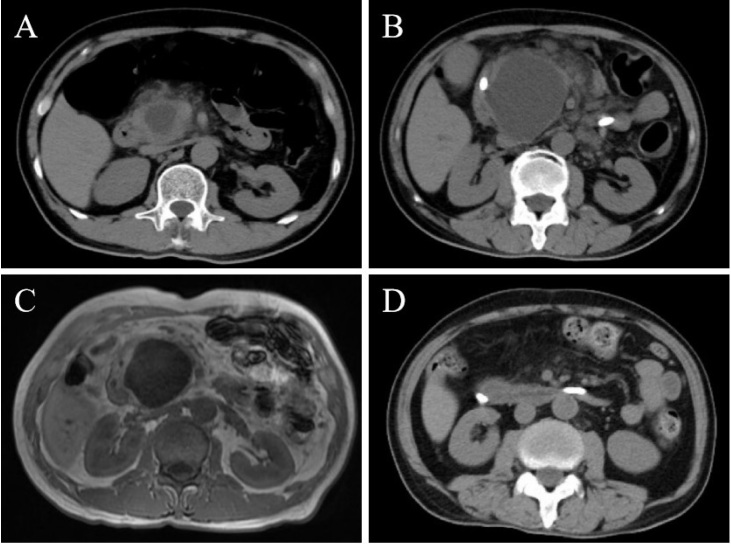

Antiphospholipid antibody-associated cystic lesion of the pancreatic head with concurrent acute pancreatitis.

并发急性胰腺炎的胰头抗磷脂抗体相关囊性病变。